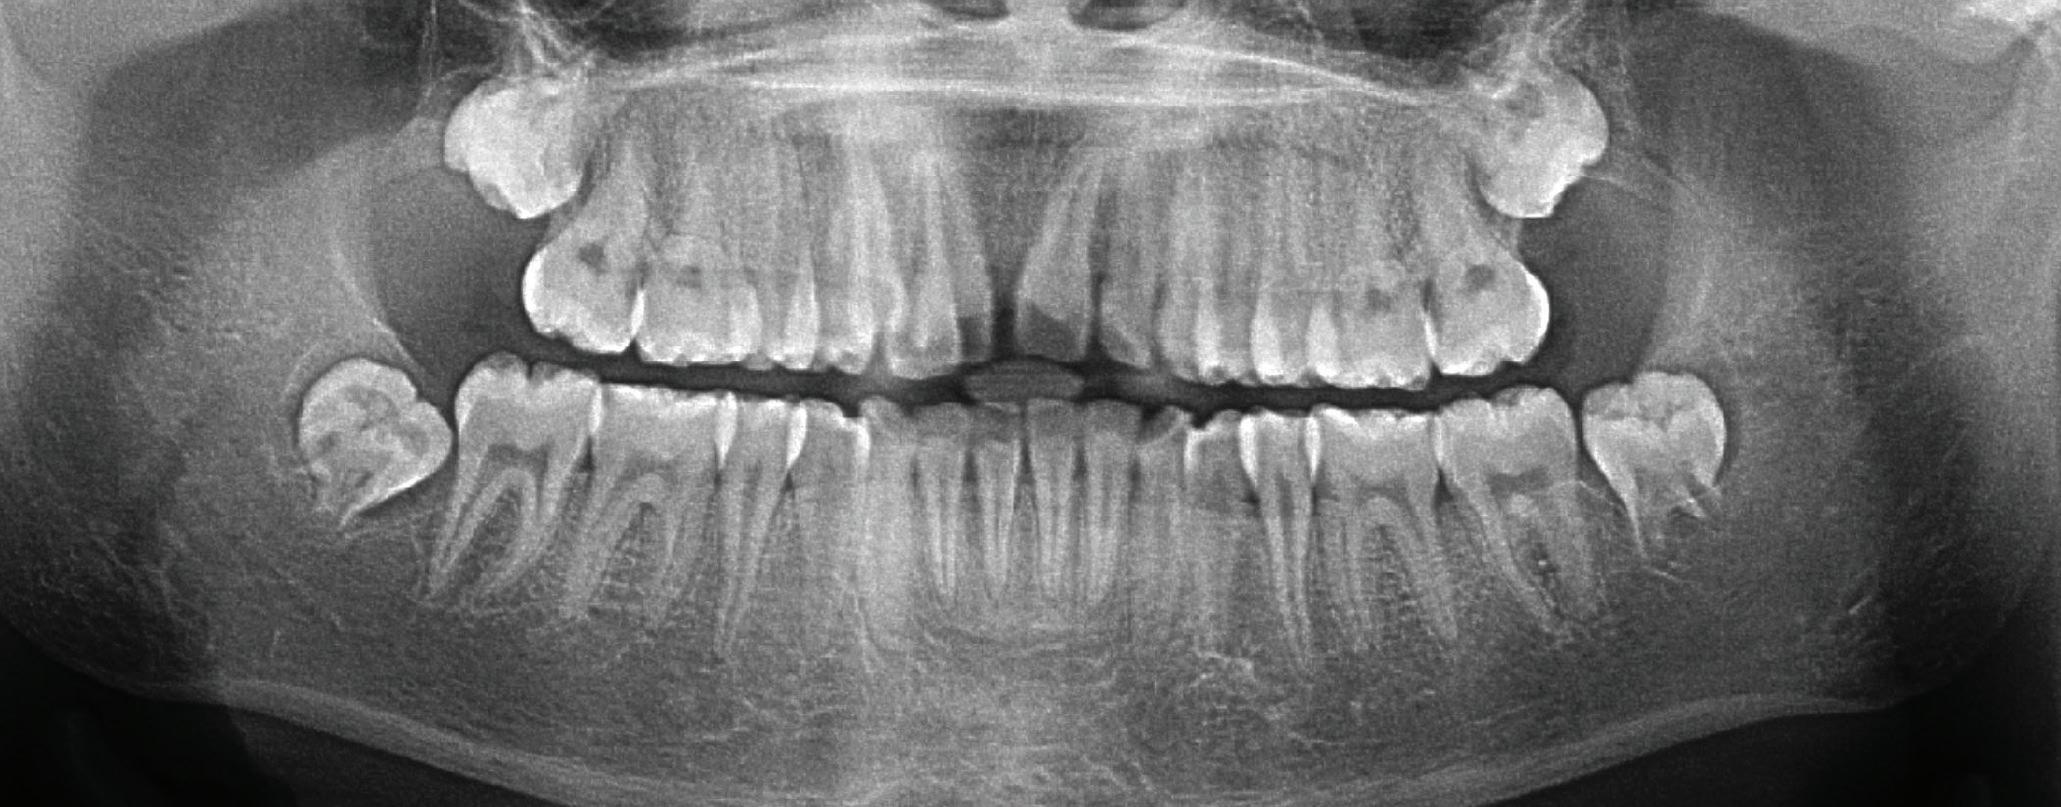

A healthy 10-year-old boy, accompanied by his mother, sought treatment of his mandibular right first molar because of pain in response to cold stimuli but reported no spontaneous pain in this tooth. Clinical examination revealed a carious lesion involving the occlusobuccal surfaces, and the tooth also appeared hypomineralized on the affected surfaces (Fig 1). The tooth responded positively to sensitivity tests, including the electric pulp test and cold test (Endo-Frost, Coltene), and there was no lingering pain or pain on percussion. A preoperative radiograph showed a large carious lesion extending to the pulp, incomplete root formation, and no pathologic periapical lesions (Fig 2). Therefore, the initial preoperative diagnosis was reversible pulpitis. The patient and parent were informed of possible pulp exposure, and VPT treatment after pulp exposure was explained in detail. Written consent for VPT was obtained from the parent.

deep caries, exposed pulp, and incomplete root formation but no pathologic periapical lesion.

The patient did not present for the 6-month recall but did present 19 months after partial pulpotomy for an orthodontic consultation at the orthodontic clinic of the same institution. At this visit, the patient reported no complaints of spontaneous or stimulated pain. Continued root development of the mandibular right first molar was noticeable in the panoramic radiograph ordered by the orthodontist, indicating that the treatment was successful (Fig 5).